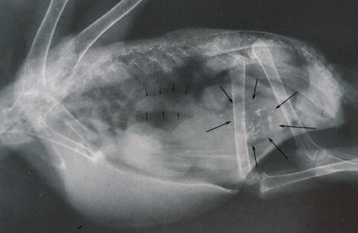

这个问题不是说问这个异宠都是什么?就是大家在接诊兔子的时候,那你碰到的主要的问题是什么?就你麻醉的时候碰到这个兔子可能出现什么主要的问题?(学员回答:兔子很应激,很难插管。)

动物怎么麻醉手术环境、对象和物种差异对异宠麻醉的影响【长文预警】_https://www.jmylbn.com_新闻资讯_第6张

兔子的肺非常小,心脏在这儿。所以在麻醉中我没有办法像其他犬一样期待这个兔子有一个很深的呼吸。它通常是一个比较浅表的呼吸,常见有胃肠道的并发症,非常小的肺 是不是?它的肠道非常大。